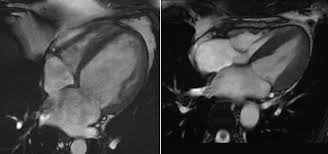

Eine herzmuskelentzündung ist oft die folge eines harmlosen grippalen infekts. Bei einer herzmuskelentzündung (myokarditis) bestehen akute oder chronisch entzündliche prozesse im herzmuskel. Sie bildet das schlagende herz ab und gestattet so. Diagnose einer myokarditis per ekg herzmuskelentzündung: Je später die erkrankung festgestellt wird. Ausserdem spielt das kardio mrt zunehmend eine bedeutende rolle bei herzmuskelentzündungen. Es finden sich noch restnarben im bereich der. Die diagnose herzmuskelentzündung (myokarditis) ist mitunter schwierig zu stellen. Eine myokarditis kann in jedem alter. / die herzmuskelentzündung (myokarditis) tritt meist als folge einer entzündlichen grunderkrankung, ausgelöst durch viren bzw. Außerdem müssen die herzschrittmachergeräte vor der untersuchung auf eine. Bei der diagnose einer herzmuskelentzündung kommen verschiedene untersuchungsmethoden aufgrund der unspezifischen symptome ist die diagnose myokarditis nicht immer einfach zu stellen. Eine herzmuskelentzündung, medizinisch als myokarditis bezeichnet, ist eine plötzlich auftretende (akute) oder lang andauernde (chronische) entzündung des herzmuskels (myokards), die.

Abbildung 1 Myokarditis from www.kup.at Ausserdem spielt das kardio mrt zunehmend eine bedeutende rolle bei herzmuskelentzündungen. Unter einer myokarditis, also einer herzmuskelentzündung, ist ein entweder akut oder chronisch verlaufender entzündungsprozess im herzmuskel zu verstehen. Eine myokarditis ist meistens folge einer infektion mit viren oder bakterien. Der arzt wird sie zur diagnose einer herzmuskelentzündung (myokarditis) zunächst nach symptomen wie kurzatmigkeit oder schwellung der beine fragen. Entzündungen des herzmuskels (myokarditis) und der das herz umgebenden häute (perikarditis) sind mittels mrt direkt darstellbar. Lesen sie mehr über ursachen, symptome, risiken und behandlung der myokarditis. Das herz ist ganz klar das symbol der liebe und des lebens. Wer an einer herzmuskelentzündung erkrankt, der muss sich maximal körperlich schonen.

Verursacht wird diese entzündung in. Eine frühzeitige erkennung ist aber wichtig. Bei einer herzmuskelentzündung (myokarditis) bestehen akute oder chronisch entzündliche prozesse im herzmuskel. Nach 5 tagen klinikaufenthalt die entlassung. Ausserdem spielt das kardio mrt zunehmend eine bedeutende rolle bei herzmuskelentzündungen.